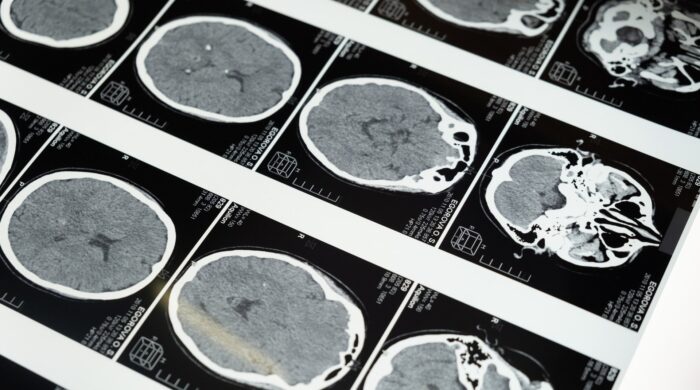

If you’ve recently been referred for an MRI, or are just curious about the procedure, you may have questions on what to expect. In this post, we’ll explore what an MRI test is, what happens during the procedure, what the results may reveal, and how you can schedule your MRI…